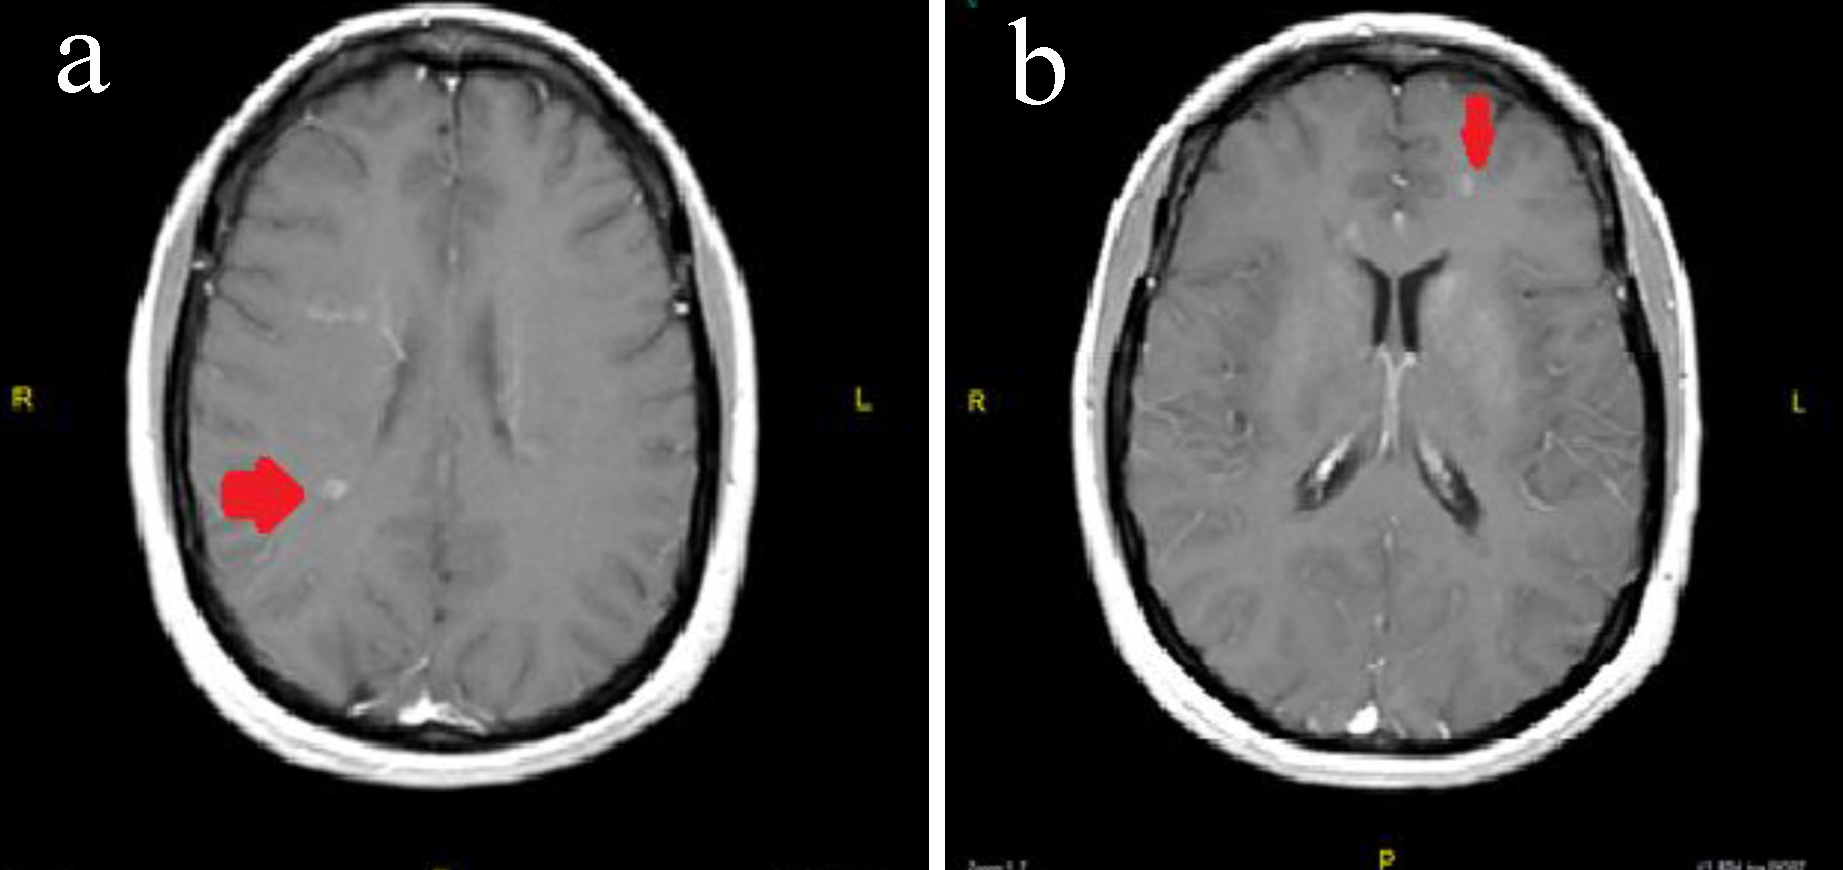

J Neurol Res

https://www.neurores.org/tables/jnr286w-g002.jpg

Figure Brain MRI With And Without Contrast Download Scientific Diagram

https://www.researchgate.net/publication/344282508/figure/fig1/AS:11431281081111555@1661533445082/Figure-Brain-MRI-With-and-Without-Contrast.ppm